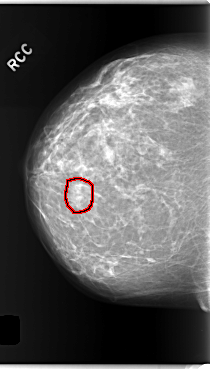

C_0286_1.RIGHT_CC

RIGHT_CC LINES 5904 PIXELS_PER_LINE 3352 BITS_PER_PIXEL 12 RESOLUTION 50 OVERLAY

FILE: C_0286_1.RIGHT_CC.OVERLAY

TOTAL_ABNORMALITIES 1

ABNORMALITY 1

LESION_TYPE MASS SHAPE OVAL MARGINS OBSCURED

ASSESSMENT 3

SUBTLETY 4

PATHOLOGY BENIGN

TOTAL_OUTLINES 1

BOUNDARY